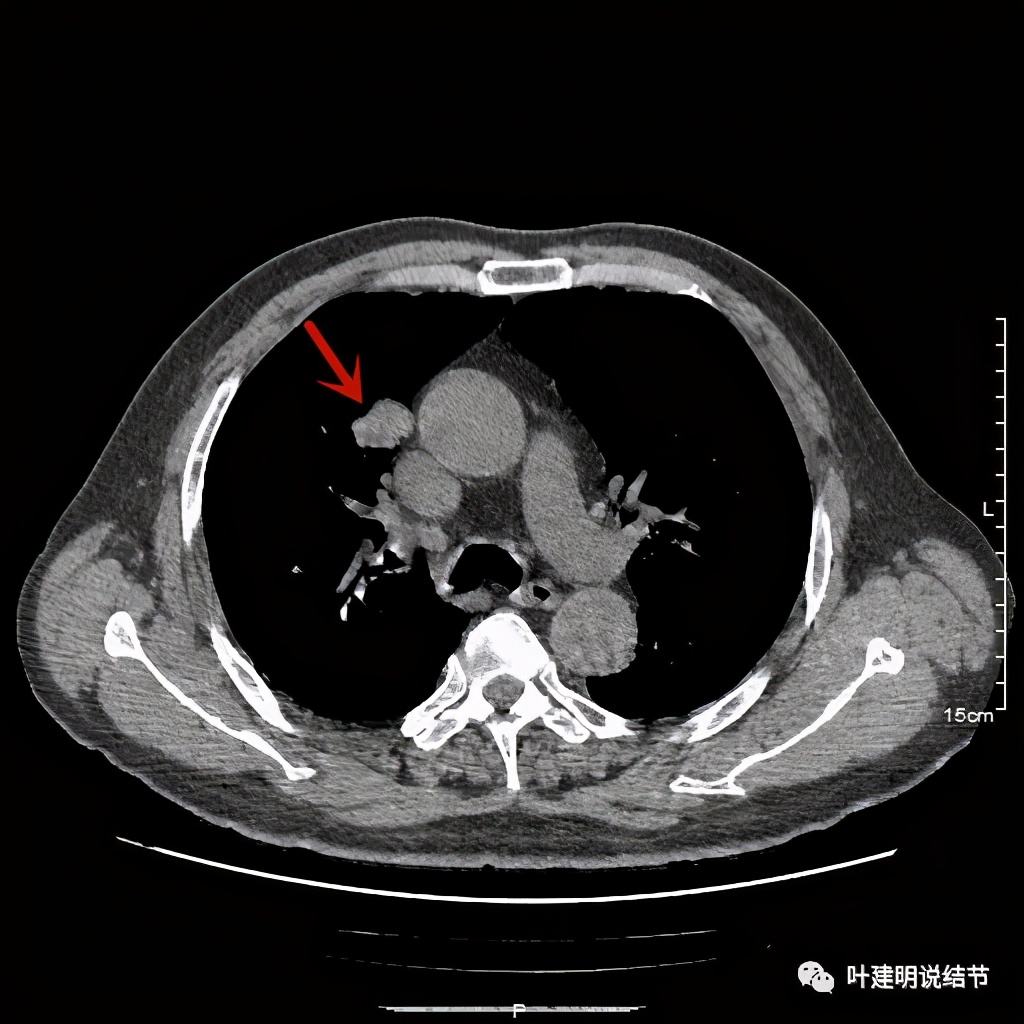

上图示病灶边缘过于光滑(绿色);局部有点状钙化(蓝色)

上图示病灶边缘过于光滑(绿色);血管贴边(桔色);

上图示病灶边缘过于光滑(绿色);血管贴边走行(桔色)

以上几图也示病灶边缘过光(绿色);血管贴边,感觉没受侵犯(桔色)